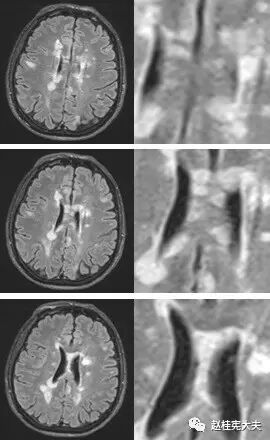

图5. 示双侧放射冠区、侧脑室旁多发圆形、卵圆形或斑片状病灶,T2高信号,部分呈煎蛋征(双娇煎蛋)。(左侧侧脑室旁)病灶长轴与侧脑室长轴垂直。

图6. T2FLAIR薄层示双侧侧脑室旁、胼胝体多发斑片状高信号灶。

多发性斑块在MR上表现为多灶性T1WI等或低信号,T2加权图像(FLAIR序列上尤为明显)上特征性不同程度的高信号,可反映脑灰、白质炎症病变;部分病灶在增强图像上表现为局灶性钆对比增强性信号改变,反映局部急性血脑屏障破坏和活动性炎症反应;较大的活动性斑块在DWI上亦可显示弥散受限。

位于脑室周围典型者,长圆形病灶的长轴与大脑或侧脑室长轴垂直,且有一狭窄正常信号带将病灶与侧脑室分开,而之后转为正常表现的低信号提示髓鞘再生;在疾病晚期,病变可发生融合,T2上出现融合性高信号灶,易误为肿瘤;因病灶可沿室管膜静脉从脑室表面进入邻近白质,故胼胝体常首当其冲罹病,且好发于胼胝体内侧或深部,即靠近脑室边缘处。